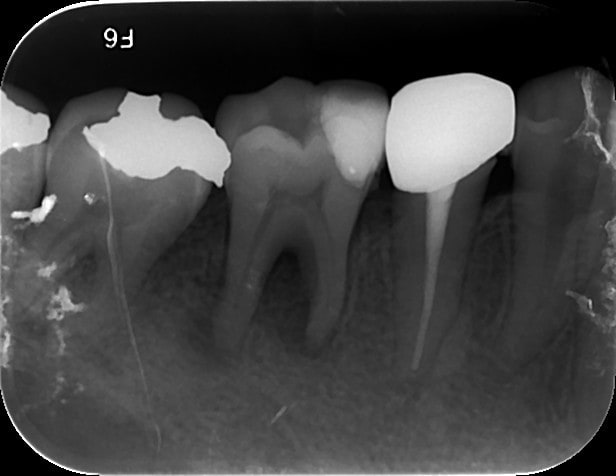

Parfois, les soins conservateurs aboutissent plus rapidement à des lésions apicales... 36 et 46 même patient, même résultat! Arrivé en urgence avec une cellulite très importante côté de gauche...

N crose pulpaire 46   01122014 vjykji - Eugenol

N crose pulpaire   11122014 m74z40 - Eugenol

N crose pulpaire   01122014 acyqev - Eugenol